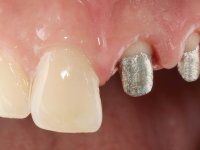

Foi feito o tratamento endodôntico dos dentes 2.1 e 2.2.de imediato, a sintomatologia que o paciente manifestava a isso impunha. Na mesma consulta foi realizada uma extensa gengivetomia com o bisturi elétrico, no sentido de expor os limites cervicais da fratura. Foram colocadas resinas compostas nos remanescentes radiculares com a intenção de reformular a emergência dos tecidos moles. Realizei a impressão dos remanescentes radiculares para confeção em laboratório de uma ponte provisória. A ponte provisória de 2 elementos, apresentava um formato que visava no futuro acomodar o coto dos espigões falsos cotos que iria ser cimentados nos remanescentes radiculares. Apresentava um reforço metálico palatino e dois apoios para os dentes adjacentes, um mesial e outro distal. Os remanescentes radiculares foram preparados para a confeção de dois espigões falso coto fundidos. As linhas de acabamento cervical foram definidas e os canais radiculares desobturados e preparados. A impressão foi realizada com a utilização de tutores de plástico com a técnica de dupla mistura. O afastamento gengival foi feito utilizando pasta de caolino. A ponte provisória foi rebasada em boca com acrílico auto polimerizavel, cimentada provisoriamente sobre as raízes e os apoios colados aos dentes adjacentes. No laboratório foram confecionados os E.F.C. fundidos, tendo o cuidado de preservar espaço para a definição no re preparo dentário da linha de acabamento cervical. Removida a ponte provisória foi feita a cimentação dos E.F.C. fundidos com cimento de ionómero de vidro reforçado com resina. A ponte provisória teve que ser retocada para permitir a acomodação dos cotos e simultaneamente foi readaptada à redefinida linha de acabamento cervical. Durante 2 meses a ponte provisória acompanhou a estabilização periodontal das raízes traumatizadas e simultaneamente conseguiu a maturação da arquitetura gengival.